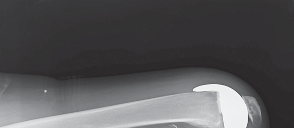

2. التصوير بالأشعة السينية (X-ray):

تُعد الأشعة السينية هي الأداة التشخيصية الأساسية لتقييم خشونة الركبة. يلتقط الأستاذ الدكتور هطيف صورًا للركبة من زوايا مختلفة، بما في ذلك صور الوقوف (Weight-bearing X-rays)، والتي تُظهر المفصل تحت تأثير وزن الجسم الطبيعي. تُظهر الأشعة السينية ما يلي:

- تضييق المسافة المفصلية: خاصة في الجانب الإنسي للركبة، مما يشير إلى تآكل الغضروف.

- تكون النتوءات العظمية (Osteophytes): وهي نتوءات عظمية صغيرة تتشكل حول حواف المفصل نتيجة للتآكل.

- تغيرات في كثافة العظام: مثل التصلب تحت الغضروفي (Subchondral Sclerosis).

- درجة الانحراف التقوسي: قياس الزوايا المحورية للساق لتحديد مدى التقوس بدقة.